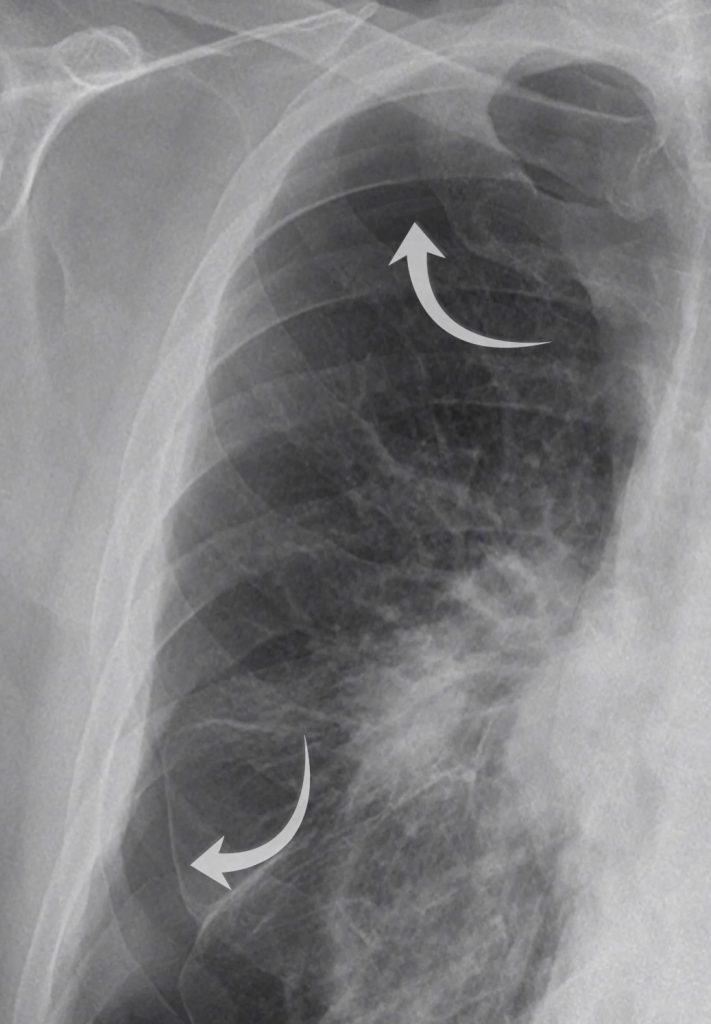

Here we have a PA chest X-ray with a lot going on. Did you notice the right-sided pneumothorax?

Going back to our case you will see a clear pleural line at the right lung apex whilst there is also a component at the right lung base, which is less commonly seen.

Did you spot the white pleural line both at the apex and within the right lower zone?

We can also see an air-fluid level at the right lung base – this represents a ‘hydropneumothorax’ ie there is both fluid and gas within the pleural space. Note how this appears slightly different to a standard pleural effusion where you get a ‘meniscus sign’ rather than a straight air-fluid level – this is because there is no surface tension from air in a hydropneuomothorax.

With a hydropneumothorax given the lack of surface tension we commonly see an air-fluid level rather than a meniscus sign that we see with a pleural effusion.

There isn’t just a pneumothorax in this case, the underlying lung looks abnormal. Looking closely we can see a right mid zone opacity and a second opacity behind the right hilum (see the image below).

Look closely and you will find two opacities within the right mid zone, one within the right mid zone and another overlying the right hilum.